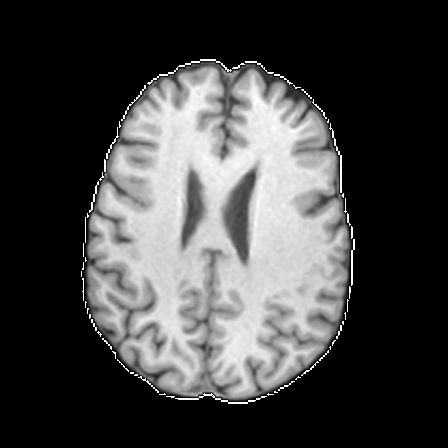

Qualitative evaluation.

To provide a more intuitive observation of our medical vision generalist, we provide the visualization of different tasks in Figure 4.